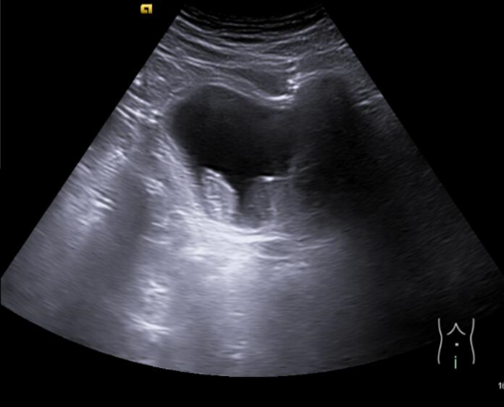

En ecografía clínica de aparato urinario se objetiva a nivel de vejiga imagen hiperecogénica dependiente de pared que no se moviliza con la movilización del paciente y no capta con modo Doppler color.

Ecografía aparato urinario agosto 2024: Litiasis en cáliz medio izquierdo de 6 mm, lesiones vesicales, próstata de 45 g.

Cistoscopia agosto 2024: Descripción de hallazgos vesicales: Lesión papilo-sólida en fondo vesical con calcificaciones en su superficie, de aproximadamente 1-1,5 cm de tamaño.